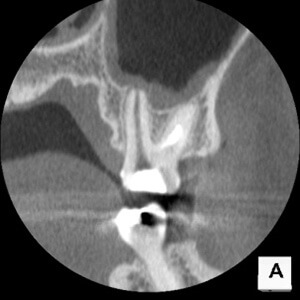

B.手術用顕微鏡を用いた治療

手術用顕微鏡を用いることにより、肉眼のみでは見ることのできないところを明確に観察しながら処置を行うことができます。このことにより診断や処置の精度をより向上させることができます。歯の根の治療では通常の治療を行っても症状が改善されない場合に、小さな根の先端部を外科的に切断除去したのち封鎖する手術(歯根端切除手術)を行うことがありますが、そのような精密な手術にも手術用顕微鏡はとても有効です。当院では、この歯根端切除手術を、診断精度の高いコーンビームCT(歯とその周囲のCT)と併用して行っています。

コーンビームCTにより高精度な画像診断ができます。